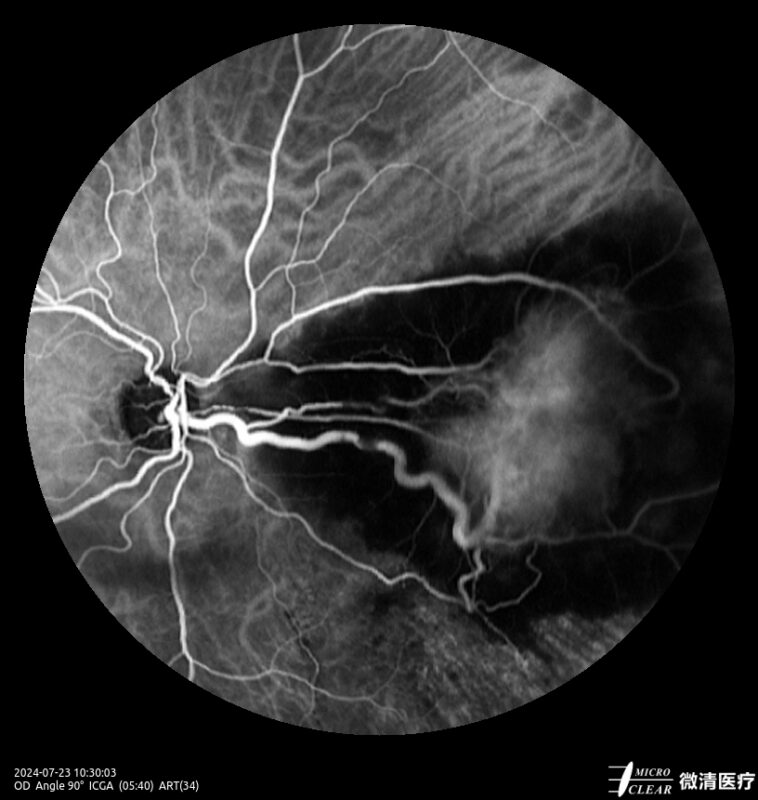

Ultra-groothoek en multimodale fundusangiografie gebaseerd op confocale scanning laser oftalmoscopie (CSLO).

- Fundusfluoresceïne-angiografie (FFA)

Confocale Scanning Laser Oftalmoscoop (CSLO)

- Combinatie van drie confocale laserbronnen voor maximaal contrast en getrouwheid.

- Verbeterd confocaal ontwerp zorgt voor een betere scheiding van de netvlieslagen en verbeterde penetratie door cataract en oculaire troebelingen.